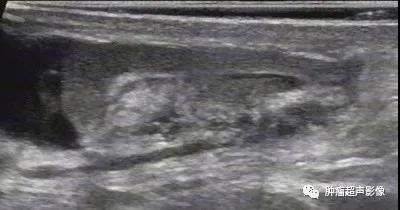

急性附睾尾部炎:右侧附睾尾部不均质肿大,血流丰富,中央见坏死区,无血流;睾丸鞘膜腔积液。